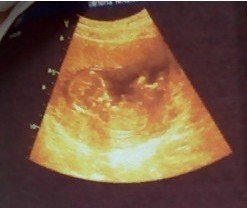

哪位高手帮我看一下,这是3个月的B超,是男宝还是女宝??? 点击展开 匿名用户 2012-11-13 13:04 满意回答 仅供参考:你当时确认怀孕时照的b超毫团,胎儿如果是一条线型一般是密斯恨男孩;圆形是女孩;其实男女都破脚一样的。 匿名用户 2012-11-14 17:06 宝宝知道提示您:回答为网友贡献,仅供参考。 为您推荐: 其他回答 是男孩。 匿名用户 2012-11-14 17:31 看 胎盘直径 不能说 匿名用户 2012-11-14 16:46 三个月看不出来吧,起码也要4个月 匿名用户 2012-11-13 14:50 相关问题 本人怀二胎了,下面是B超单,请各位高手看一下是男宝还是女宝,谢谢了! 请教高手!帮我看一下怀孕25W+3做的胎儿三维B超报告? 我老婆怀孕后做的b超,请各位高手帮看一下